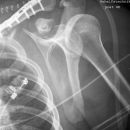

Dislozierte subcapitale Fraktur mit Tbc majus